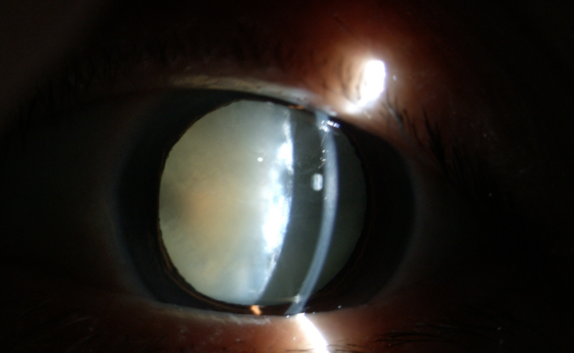

白內(nèi)障癥狀

糖尿病患者合并白內(nèi)障盡早手術(shù)的原因:白內(nèi)障發(fā)生后,不但使患者視力產(chǎn)生障礙甚至失明,還直接影響到醫(yī)生對眼底的檢查和治療,因為渾濁的晶狀體阻斷了進出光線。因此,糖友們的白內(nèi)障手術(shù)治療,既能解除視力障礙,還能掃除糖尿病視網(wǎng)膜病變的檢查、治療障礙,所以應(yīng)盡早手術(shù)。